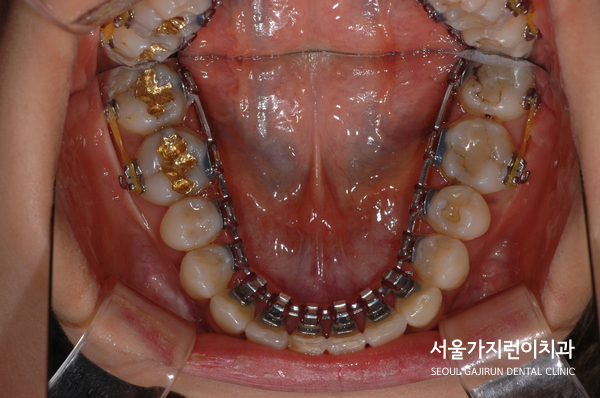

교정으로 할 때 임플란트의 존재와 임플란트 주변의 치아이동에 제한이 있다는 점을 염두하고 치아교정 계획을 수립해 진행하기로 했습니다. 또한 설측교정 방식을 적용해 치료를 진행했는데요. 두 개의 와이어로 설측탄댐교정을 진행해 치아이동에 필요한 힘을 안정적으로 주었습니다. 여기에 잇몸에 미니스크류를 식립해 고정원으로 삼고 이동을 시켰는데요.

임플란트한 치아가 움직이지 않도록 최대한 노력했고 다행히 임플란트도 이상 없이 유지되면서 교정을 마칠 수 있었습니다.

말끔하게 해결된 것을 확인할 수 있었습니다. 임플란트도 이상없이 안정적으로 유지된 것을 볼 수 있는데요.